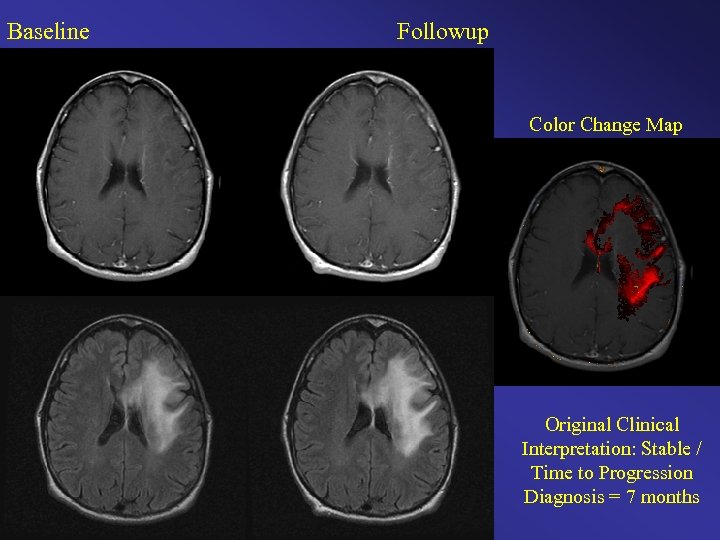

Baseline Followup Color Change Map Original Clinical Interpretation: Stable / Time to Progression Diagnosis = 7 months

Baseline Followup Color Change Map Original Clinical Interpretation: Stable / Time to Progression Diagnosis = 3. 25 months